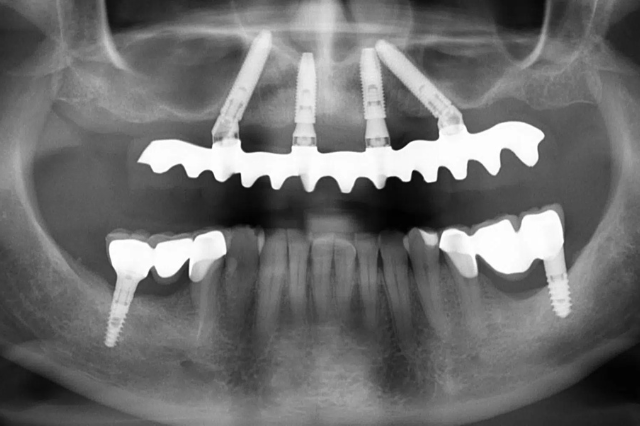

Implantációs fogpótlás – teljes rehabilitáció

AllOn4 és AllOn6 implantációs megoldással, halasztott implantációval és azonnali megterheléssel készítettünk rögzített ideiglenes pótlásokat.

allon4_OP_P1

rtga4_mutet_utan1